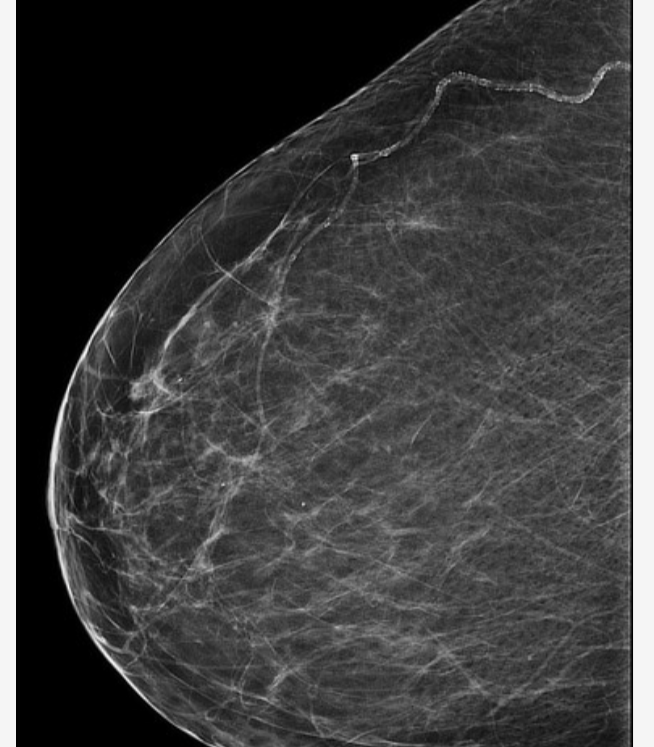

O tom, že hustá prsní tkáň může představovat o 1,2 až 4 % vyšší riziko rozvoje rakoviny prsu, vědělo jen 6 z 61 dotazovaných žen. Většinu z nich na to, že mají vysoký podíl husté prsní tkáně, přitom upozorňovali lékaři během mamografu. Čím je totiž hustota prsní tkáně větší, tím je navíc obtížnější na mamografickém snímku zhoubný nádor či jiné změny objevit.

Vysoká denzita prsní tkáně (nebo též mamografická denzita) představuje zvýšené riziko vzniku rakoviny prsu; podle výsledků dalšího výzkumu však pacientkám s rakovinou prsu, které mají vysokou mamografickou denzitu, nehrozí zvýšené riziko úmrtí na toto onemocnění. Výsledky výzkumu, který vedla dr. Gretchen L. Gierachová z amerického Národního onkologického ústavu (National Cancer Institute, NCI) a který se uskutečnil ve spolupráci s odborníky z Breast Cancer Surveillance Consortium (BCSC), byly publikovány v odborném časopise Journal of the National Cancer Institute.